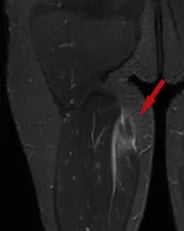

As lesões nos músculos e tendões na coxa geralmente ocorrem após um trauma ou movimento abrupto, relacionado a atividades esportivas. A Ressonância Magnética confirma o diagnóstico.

Lesão do quadríceps: ocorre frequentemente no momento de um chute, acometendo geralmente o reto femoral. Lesões tendíneas costumam causar dor no quadril, enquanto lesões na fibra muscular causam mais dor na coxa. Seu tratamento é com repouso e Fisioterapia na grande maioria dos casos.

Lesão dos isquiotibiais: são os músculos da parte de trás da coxa (semitendíneo, semimembranoso e bíceps femoral); a lesão geralmente ocorre ao se esticar o quadril com o joelho estendido, fazendo com que o paciente sinta dor na parte baixa da nádega ou na coxa, dependendo do local da lesão. Tratam-se as lesões das fibras musculares com repouso e Fisioterapia. Já avulsões tendíneas, podem necessitar de cirurgia, caso haja avulsão de 2 tendões ou mais, com retração maior de 2 centímetros.